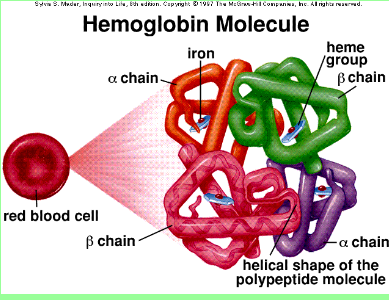

Heme | definition of heme by Medical dictionary

Heme binds and carries oxygen in the red blood cells, releasing it to tissues. Also spelled haeme. See also hemoglobin, porphobilinogen, protoporphyrin.

….. blood IRON Heme Fe(2) group software / the living languages

inside N = Nitrogen H = Hydrogen

Fe = Ferrous oxide IRON software ….